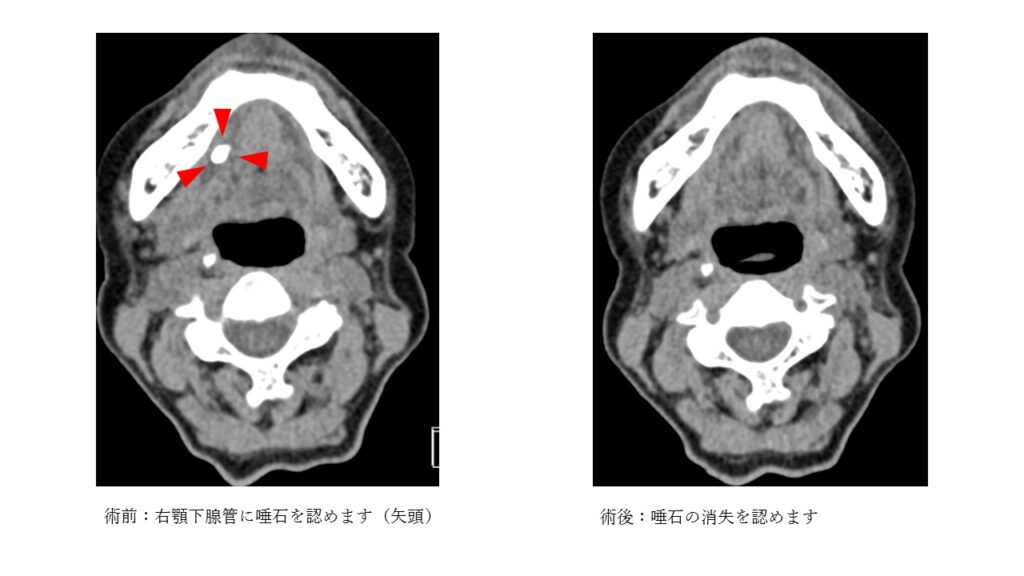

特に顎下腺で唾石ができやすく、自然に排石せず残ってしまうことが多いです。従来は顎下腺摘出術や口腔内を切って唾石を摘出していました。

唾液腺管内視鏡は直径2mmほどの内視鏡で、唾液腺管に挿入して唾石をみつけ内視鏡より鉗子(ピンセットのような器具)で摘出します。すこし、口腔内を切開する必要がありますがお顔やくびに傷をつけることなく手術を行える利点があります。手術は全身麻酔で行い、2時間以内となります。手術翌日より食事を摂っていただき、術後3日目くらいには退院となります。